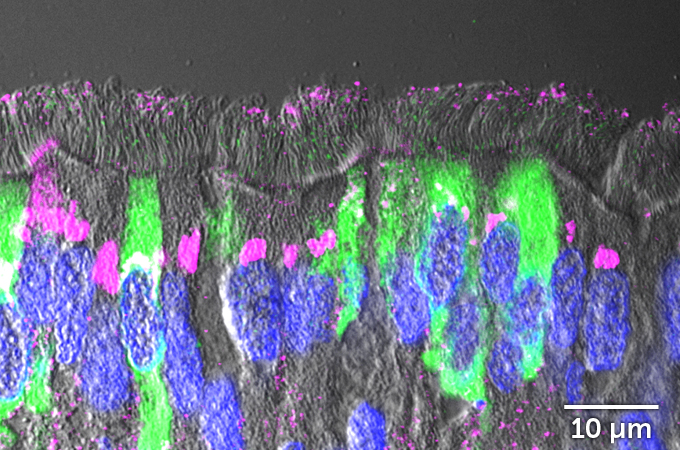

But not all the cells in the infected lawn were affected equally. Looking at the cells from the side, researchers could see that cells sporting cilia were infected with the coronavirus. But mucus-producing cells called goblet cells, which don’t have cilia, were rarely infected. That may be because a protein called ACE2 decorates the surface of ciliated cells far more often than it does goblet cells. ACE2 is the protein that the coronavirus uses as a door into cells.

When researchers doused the cells with IL-13 before adding the coronavirus, the results were strikingly different.

The lawn of waving cilia atop the treated cells was mostly intact, with far fewer balloons of dying cells rising above the surface. But the fronds didn’t wave as vigorously as in untreated cells. That’s because IL-13 reduces cilia beating, the researchers found. Less active cilia could mean that virus-laden mucus sticks around longer. “That can be a double-edged sword inside the lungs because you want to clear the mucus, but you don’t want to spread it around,” Ehre says.

Counting cells under the microscope, the researchers saw that far fewer of the infected cells treated with IL-13 got the heave-ho. Whereas the untreated cells had ejected about 700 of their own by about four days after infection, only about 100 treated cells had gotten kicked out. The images showed that IL-13 really was protecting cells from infection. But how was still an unanswered question.

One thing that IL-13 does is stimulate airway-lining cells to churn out a type of sticky mucus that can trap viruses before they can infect cells. The team found that untreated cells released a burst of the mucus shortly after being infected with the coronavirus, depleting stores of the sticky stuff. But cells treated with IL-13 were still well-stocked with mucus.

Examining patterns of gene activity, the team found that IL-13 was also causing cells to make less ACE2, the protein that SARS-CoV-2 commandeers as a gateway into cells. “It makes it much harder for the virus to find its door to enter the cells,” Ehre says.

Cells treated with IL-13 also turn down the activity of genes involved in making protein-producing factories called ribosomes, the researchers discovered. That may limit viral replication in cells. But some genes’ activity was also turned way up. That includes several genes involved in making keratan sulfate, a long chain of sugars that is found in cartilage and the eyes’ corneas. “It’s there in the body to make a shield,” Ehre says.

That seems to be what it is doing for airway cells too. A thick layer of keratan sulfate developed on top of cells treated with IL-13, armoring them against a coronavirus infection.